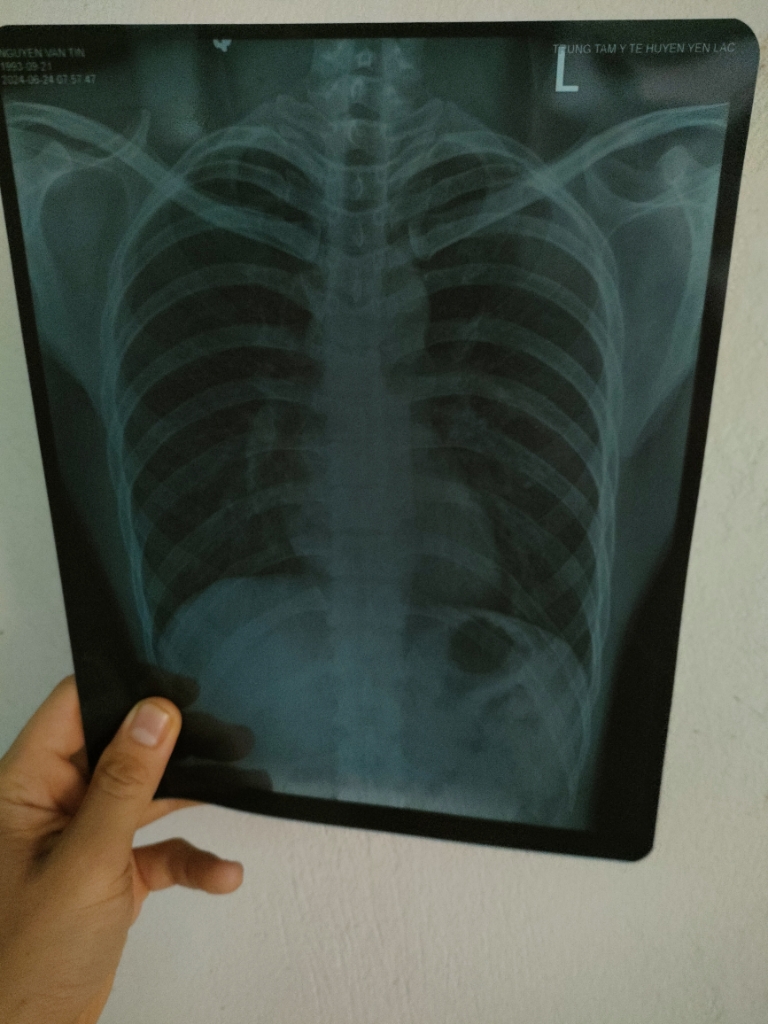

Dạ, đây là hình ảnh XQ của em ạ.